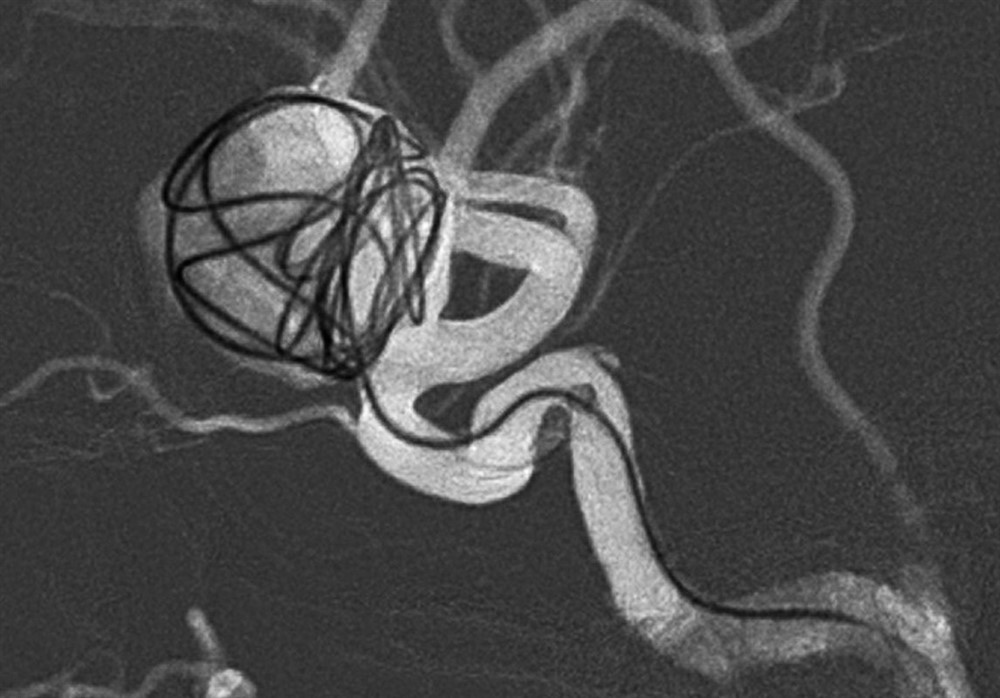

阮郁修醫師評估艾小姐的病情,採用「血流導向裝置輔助線圈栓塞術」,使用特殊導管經由鼠蹊部穿刺進去,將導管放置於內頸動脈,並透過導管將纏繞的線圈放進動脈瘤的空腔以及將血流向裝置放置於動脈瘤開口,讓動脈瘤內的血流停滯產生栓塞,重新把血流引導到正常的血管,使動脈瘤體積逐漸縮小,不再復發。

目前統計數據顯示此類手術成功率達九成以上,而術後半年有八成的動脈瘤就會栓塞,術後三年,百分之九十八的動脈瘤會完整栓塞。

阮郁修醫師以「血流導向裝置輔助線圈栓塞手術」來阻斷動脈瘤繼續生長,拆除腦內炸彈。圖/台北慈院提供